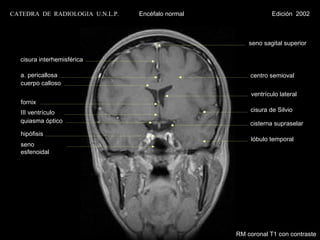

seno sagital superior

cisura interhemisférica

a. pericallosa                                       centro semioval

cuerpo calloso

ventrículo lateral

fornix

III ventrículo                                       cisura de Silvio

quiasma óptico                                       cisterna supraselar

hipófisis

lóbulo temporal

seno

esfenoidal

RM coronal T1 con contraste